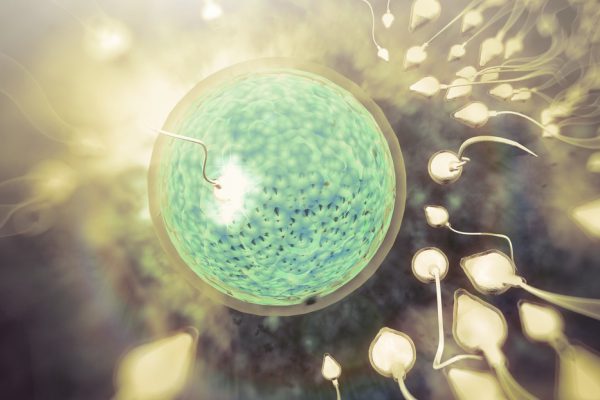

Moscú, 2 oct.- La infertilidad en los seres humanos podría tener cura, según una investigación liderada por el biólogo estadounidense Shoukhrat Mitalipov, director del Centro de Terapia Génica y de…